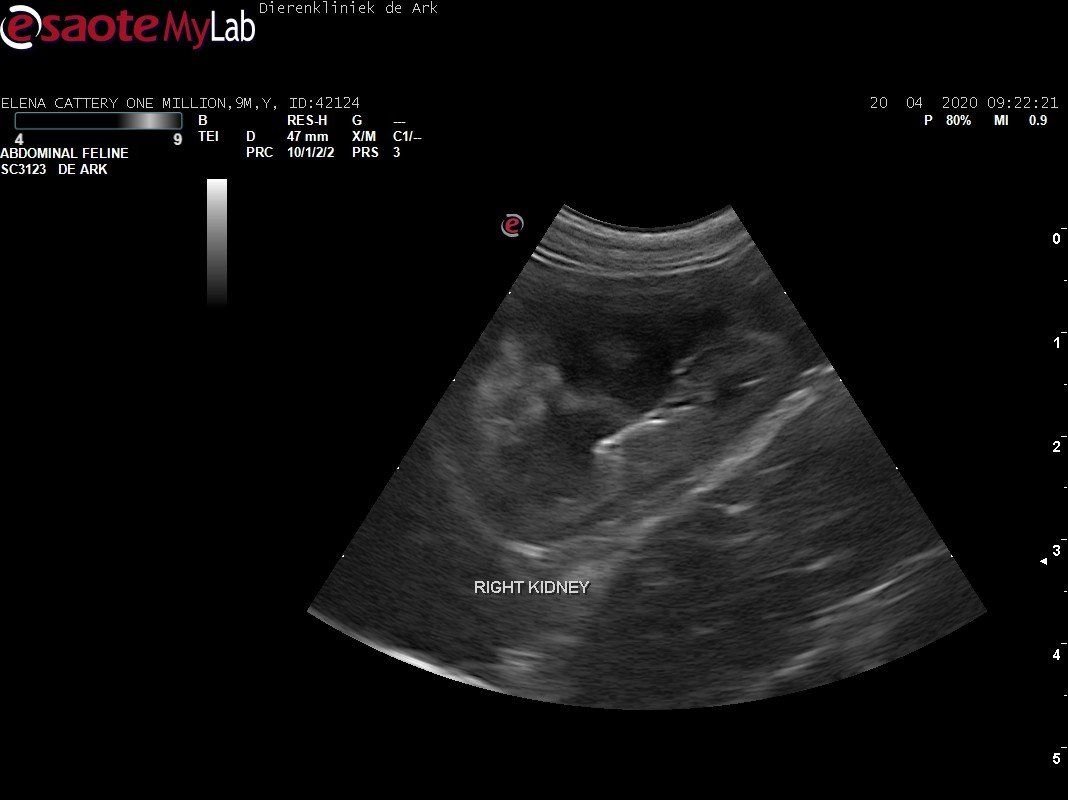

3,200 kg , echo en nieuw bloedonderzoek gedaan wat perfect ging door middel van gapabetine

Voor de garanties en om recht te hebben op medicatie bij herval eist Mutian diverse onderzoeken en controle momenten. Dit zijn bloedonderzoeken maar ook zoals hieronder te zien is echo's. Elana is volledig gecontroleerd op afwijkingen, gelukkig waren de echo's goed.